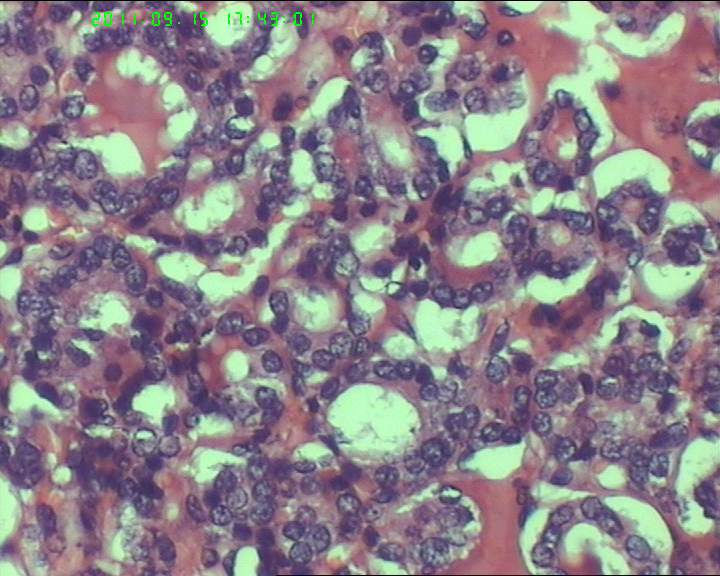

38岁女性甲状腺,腺瘤?滤泡癌?

甲状腺右下极一肿物,3*3大小,切面灰红实性质韧,可见部分包膜,一侧可见一空腔,未见内容物。

38岁女性甲状腺,腺瘤?滤泡癌?图1

名称:图1

描述:20110915-1.jpg.jpg